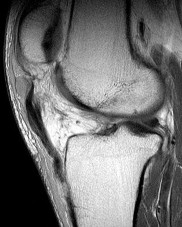

A 15-year-old male presents with chronic knee pain. MRI reveals a stable Osteochondritis Dissecans (OCD) lesion of the knee. Which of the following anatomic locations is the classic and most common site for an OCD lesion in the knee?

The classic and most common location for an osteochondritis dissecans (OCD) lesion in the knee is the lateral aspect of the medial femoral condyle (often remembered by the mnemonic 'LAME': Lateral Aspect Medial Epicondyle/Condyle). It accounts for approximately 70-80% of knee OCD lesions.